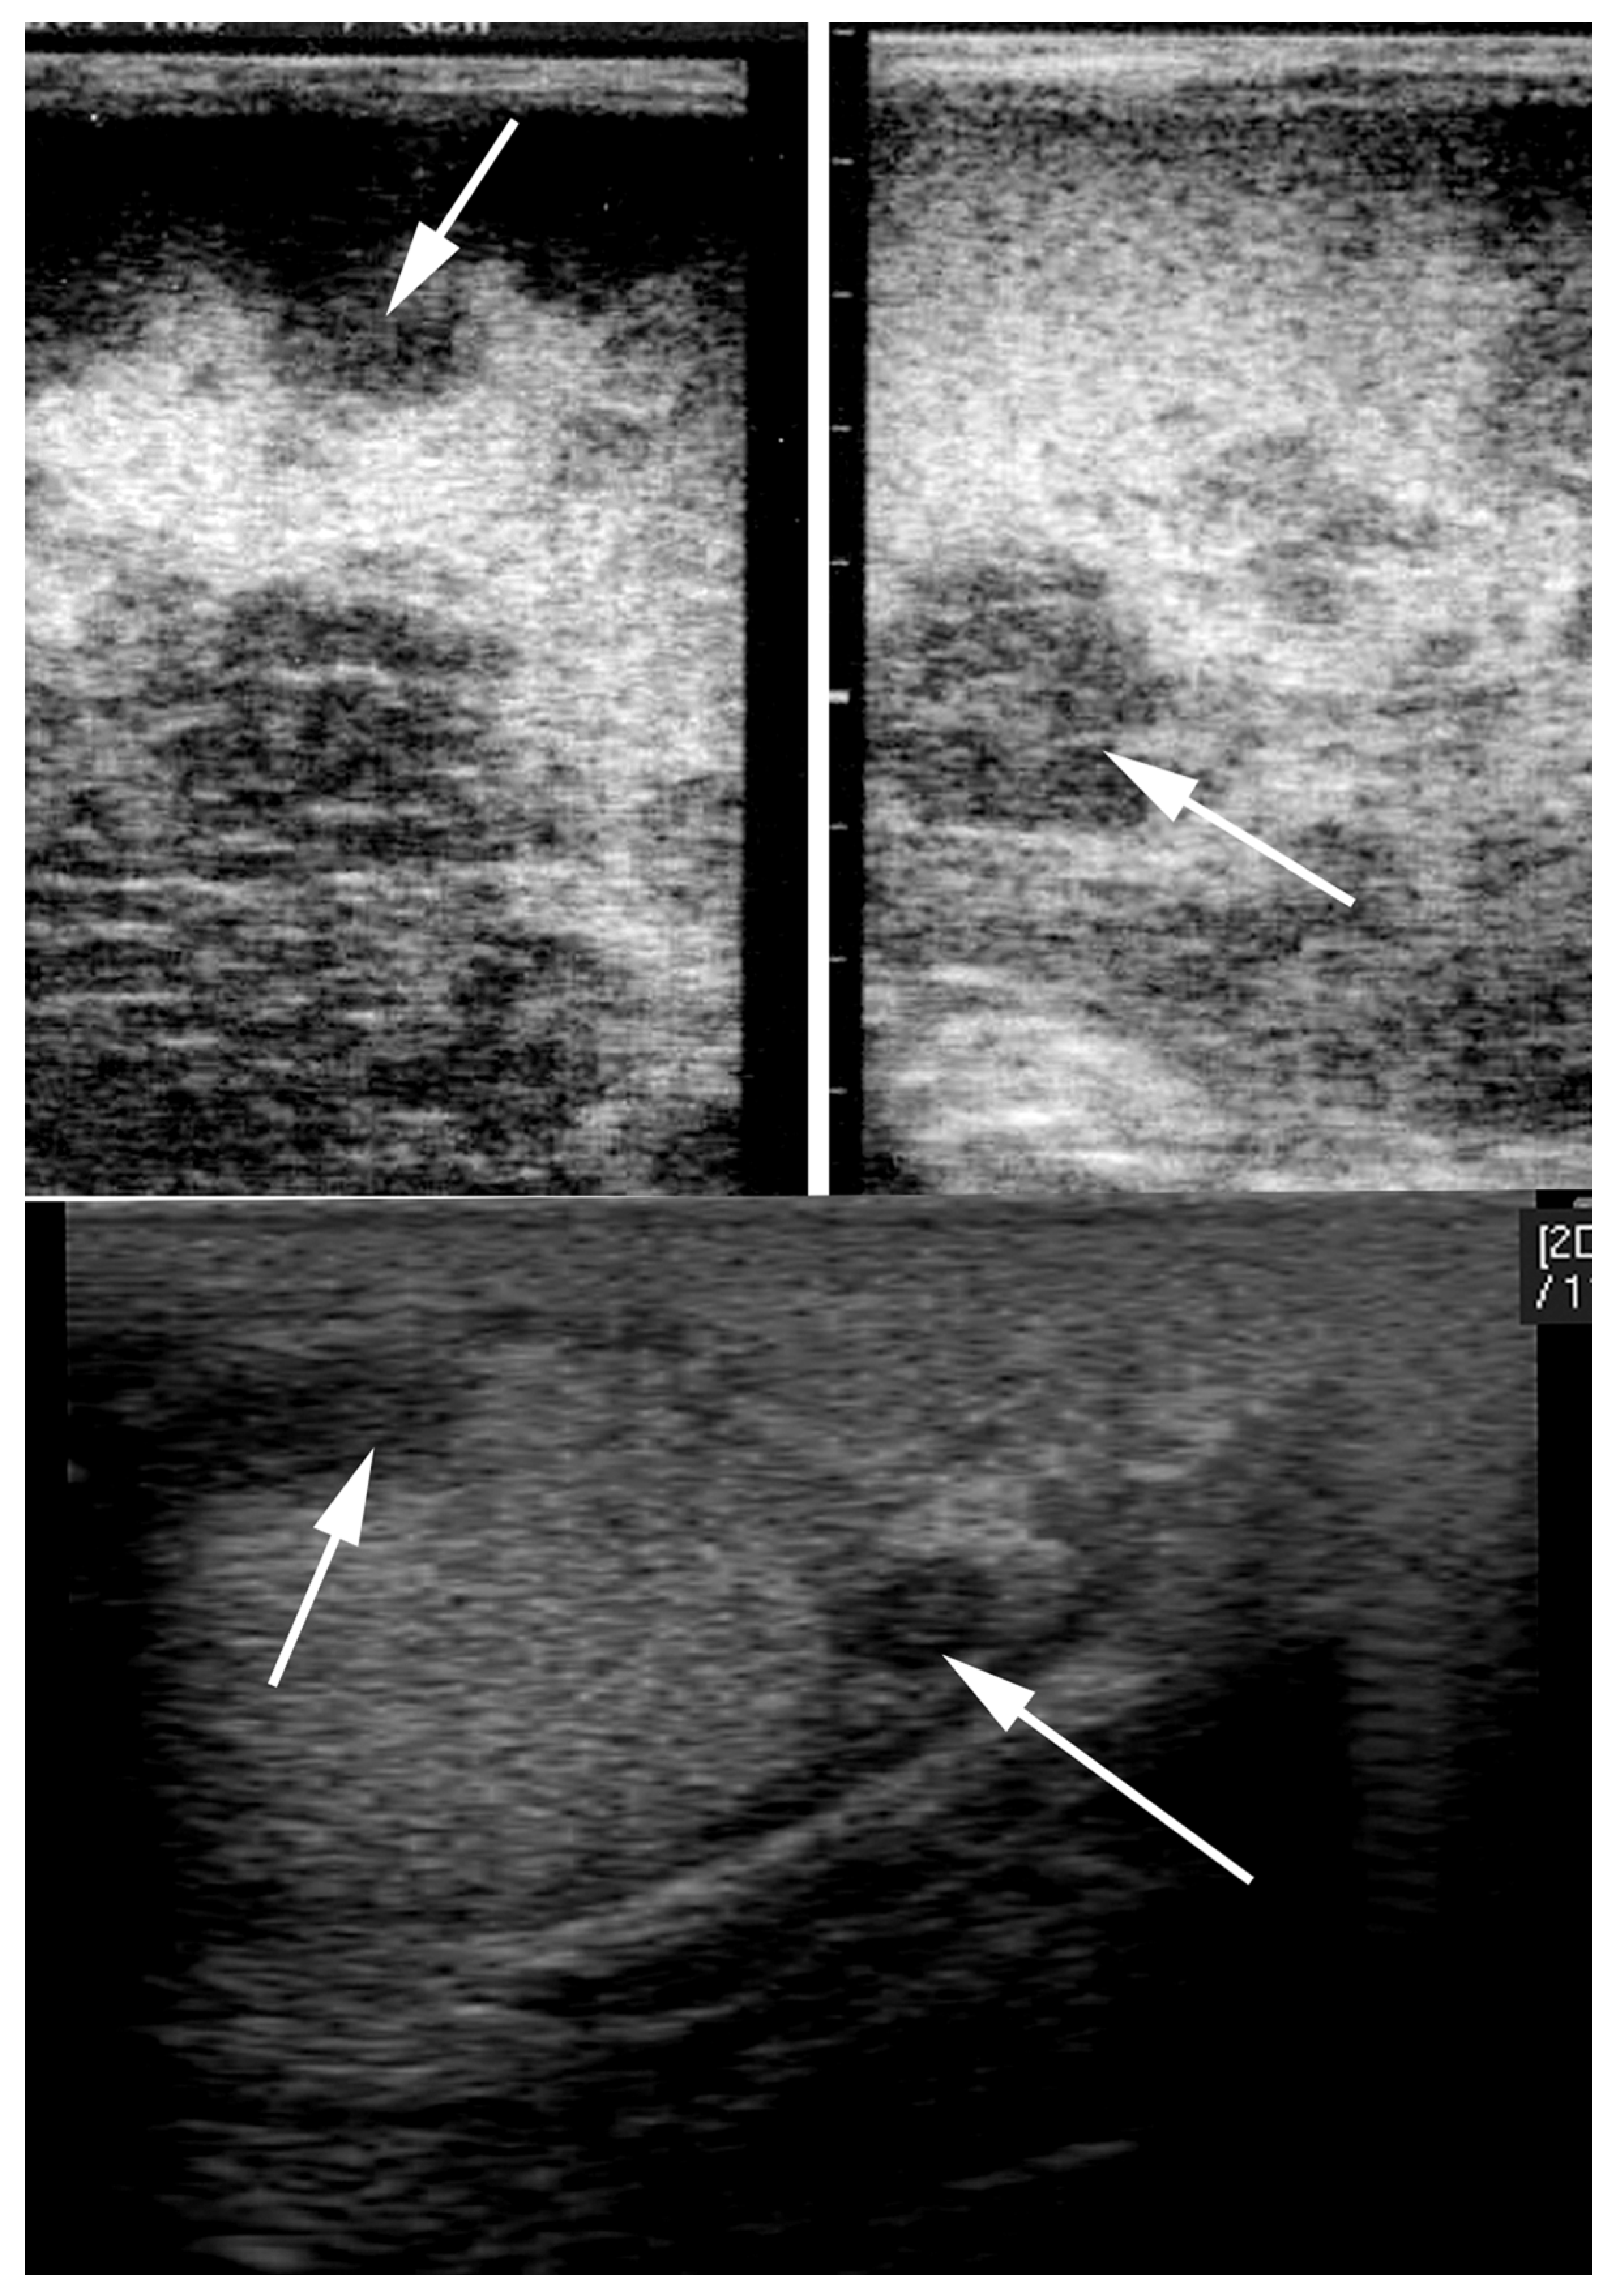

4.4. Orchitis and Epididymitis

5. Differential Diagnosis of Progressive Scrotal Enlargement

6. Asymmetric Testis/Testicular Degeneration